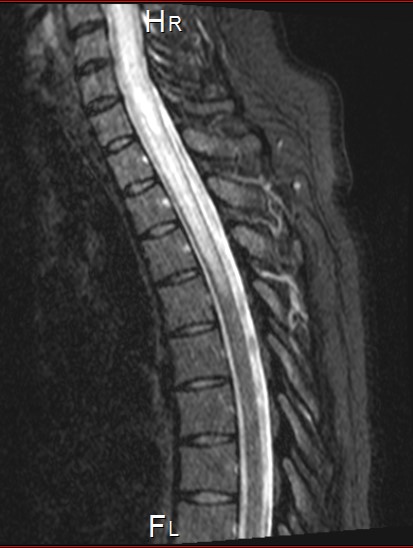

MRI studies were conducted and the local radiologist reading the MRI concluded the patient had findings consistent with a primary cord tumor (ependymoma, astrocytoma, or ganglioma).  Other considerations such as hemangioblastoma, intramedullary metastasis or lymphoma were also possible.  Intramedullary enhancement within the cord was C3 to T1 with cord expansion (C6-T1)) and extensive surrounding edema extending to T4. (see Figures 3 and 4).

Figure 3